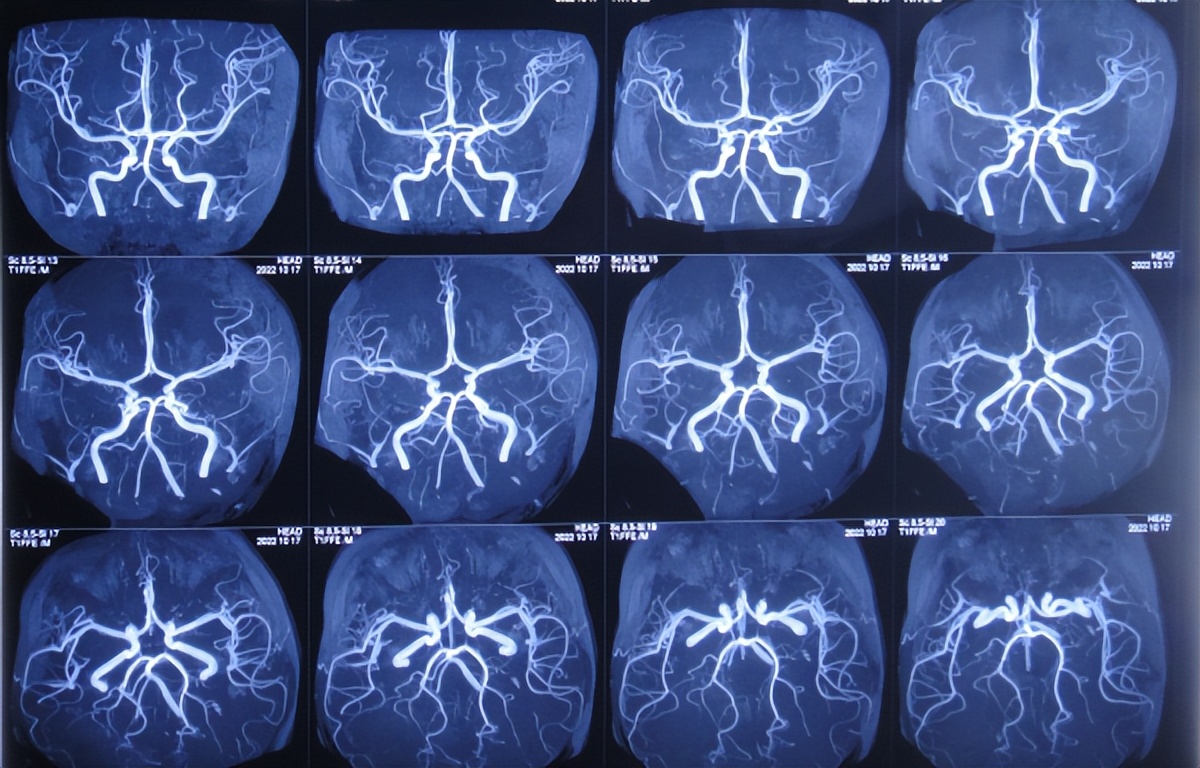

进一步检查颅脑血管造影( 图-6 )和颅脑核磁增强( 图-7 )示延髓偏后方占位伴延髓损伤,考虑中线胶质瘤伴出血可能性大。

图-6: 2022年10月17日颅脑血管造影